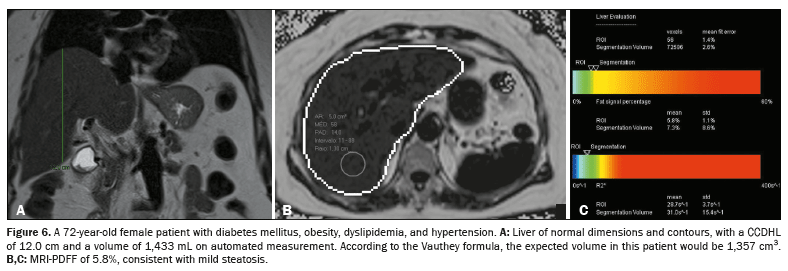

p < 0.001), reflecting the results of the previous analyses. The interaction between fat accumulation and increased liver volume is exemplified in Figures 6, 7, and 8.

Confounding factorsThe increase in the eLV according to the degree of steatosis was not significantly different according to sex (